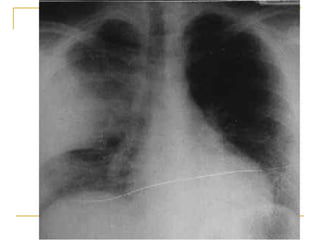

Radiografía de tórax obtenida al ingreso (compromiso intersticial   )

Radiografía de tórax control a los 5 días del ingreso (opacidades tipo “vidrio esmerilado” )